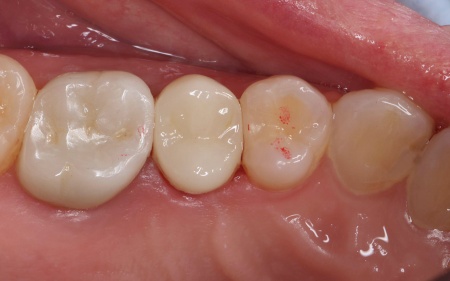

診断結果をお伝えした上で、再度根管治療を行ってから、殺菌効果の高いMTAセメントを用いて根管をしっかりと封鎖し、その後ジルコニアクラウンで修復する治療計画を提案し、同意いただきました。

ジルコニアクラウンは、人工ダイヤモンドとも呼ばれるほど高い強度と耐久性を持つジルコニアで作る被せ物です。

自然な白さと強度を兼ね備えているため、奥歯のような強い力がかかる場所に適しています。

その後、被せ物を装着するために歯の形を整え、型取りを行っています。

後日、完成したジルコニアセラミックが歯にピッタリと合っているか、噛み合わせに問題がないかを十分に確認した上で装着し、治療を終了しました。